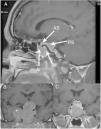

Cavernous sinus (CS) invasion is found in 15–20% of pituitary adenomas; it represents a poor prognosis factor and a surgical challenge even in experienced pituitary centers. We present our experience and technical note description for surgical management of pituitary adenomas with CS invasion in acromegaly by the transsellar lateral approach with an endoscopic endonasal transsphenoidal route.

ResultsThirty-two of 94 patients with diagnosis of pituitary adenoma treated at our institutions (34%) had acromegaly; thirteen of patients with acromegaly diagnosis met the inclusion criteria for CS invasion. Postoperative images reported gross total resection in 10 patients (76.9%). Mean follow-up time was 28.3 months. Remission criteria were achieved in nine patients (69.2%), with one of these patients (11.1%) having recurrence during follow up. All patients with no biochemical remission had improvement in GH and IGF profiles. Three patients without remission underwent radiosurgery (14Gy), and one patient had remission after the procedure.

ConclusionsWe consider this to be a safe and efficient approach for tumors invading CS, when surgical team have good experience in endoscopy of the skull base and reconstruction techniques, appropriate instruments are available, and tumor has soft consistency.